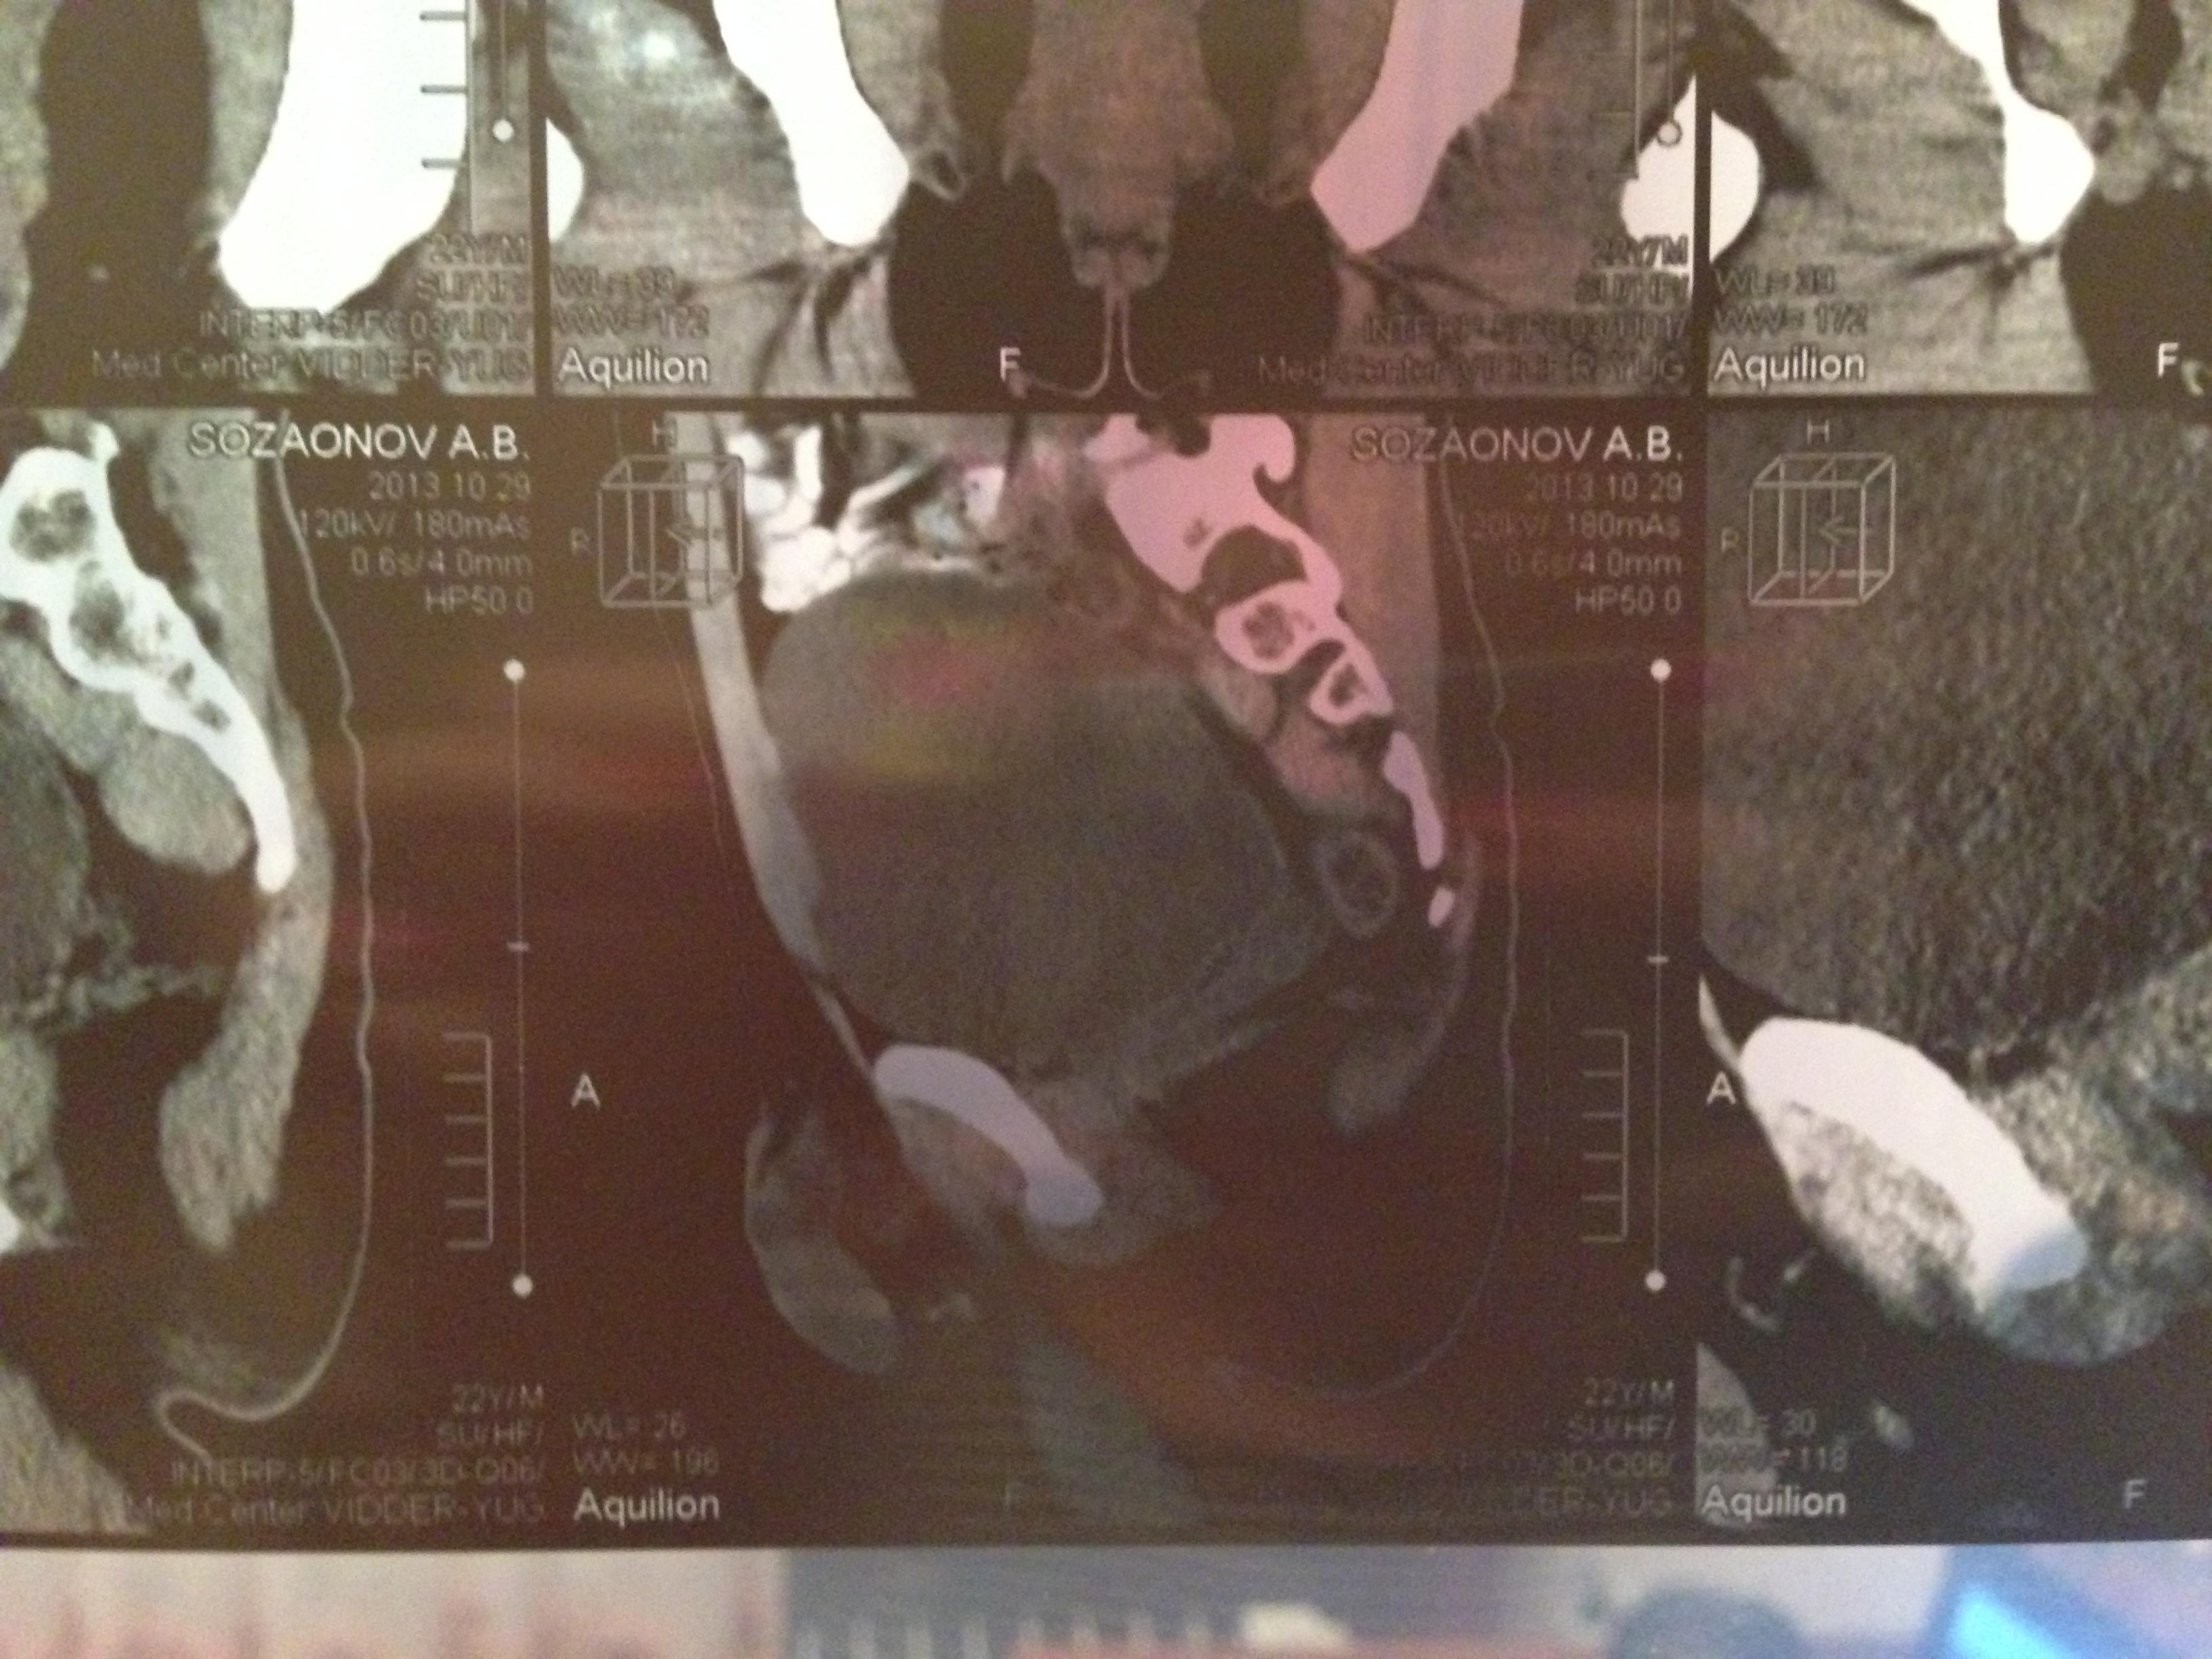

проведена МСКТ области таза!Внеорганных дополнительных патологических образований,лимфаденопатии или свободной жидкости в области таза не выявлено.

Мочевой пузырь-наполнен,стенки не утолщенны,паравезикально-без грубой органки.

Граница между предстательной железой и пузырем несколько четкая,контур пузыря на данном уровне не деформирован.

Предстательная железа-без грубой органики,еденичные микрокальцинаты.

Семенные пузырьки-конфигурация не совсем типична,примерный размер правого 26*28мм.Отмечаются признаки кистовидной трансформации и микрокальцинации обоих пузырьков.Наибольшая из кист слева достигает 9 мм.Обращает на себя внимание неравномерная кальцинация стенок крупных регионарных(текстикулярных)артерий с обоих сторон.

Костно-деструктивных изменений характерных для mts со стороны костей таза не отмечено.

Параректальная клетчатка-не изменена,патологически увеличенных лимфоузлов в параректальном пространстве не отмечено.M.m.levator ani-без особенностей.

Заключение:на момент исследования,КТ-данных за наличие внеорганных дополнительных патологических образований,лимфоденопатии или свободной жидкости в области таза не выявлено.КТ-признаки в пользу проявлений калькулезного везикулита с элементами кистовидной трансформации семенных пузырьков.